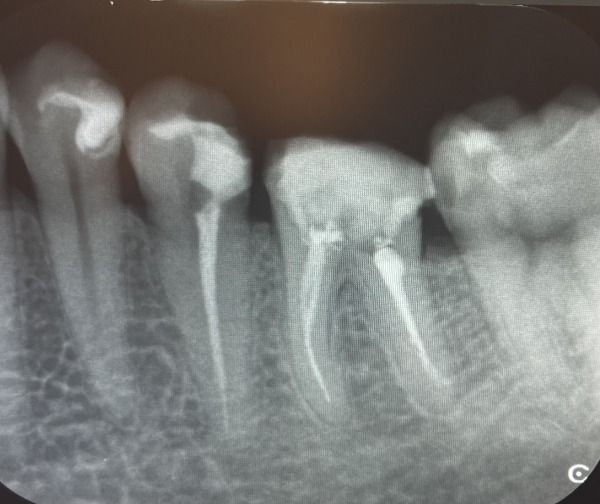

診察をしたところ、左下の奥歯2本が大きな虫歯になっていました。手前は歯の根っこだけになり、奥歯は大きく穴が開いていました。エックス線写真を撮ると、前医での根管治療後に被せ物が装着されないまま中断された状態が確認できました。また、奥歯を中心に何か所か歯と歯の間から虫歯ができていました。

1日目〜3日目 左下の歯の根管治療を行い、治療後のエックス線を撮影しました。

4日目 根管治療を終えた後に土台を立てました。

5日目 左下の1番奥の虫歯を取り除き、2本同時に型取りをしました。